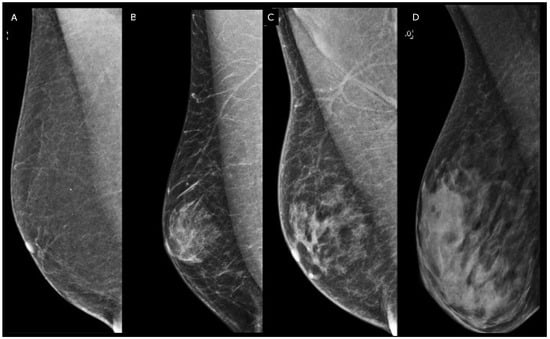

The mammographic assessment reveals three distinct patterns: nodular, dendritic, and diffuse [13]. Nodular gynecomastia is an early and reversible manifestation, appearing as a retro-areolar fan-shaped density with indistinct borders, representing hyperplasia of intraductal epithelium and stromal edema. Dendritic gynecomastia indicates the fibrotic phase, characterized by dilated ducts and hyalinized stromal fibrosis. Mammographic features include a flame-shaped density with linear finger-like projections into the subareolar fatty tissue. Diffuse gynecomastia results from chronic estrogen exposure and can exhibit features of both nodular and dendritic forms or resemble the architecture of the female breast [5]. Pseudo-gynecomastia, primarily observed in overweight or obese individuals, results from excessive fatty tissue stimulation without fibro-glandular components and is a key differential diagnosis to consider (Figure 2).

Figure 2.

Right medio-lateral-oblique digital mammography of different types of male breast. (A) Pseudo-gynecomastia: the breast is almost entirely fatty. (B) Nodular gynecomastia: in the retro-areolar region, there is a nodular density that blends into the surrounding subcutaneous fat, resulting in indistinct border. (C) Dendritic gynecomastia: there are fibrous extensions of dendritic gynecomastia (flame shaped) in the breast. (D) Diffuse gynecomastia: heterogeneously dense breasts consisting of both nodular and dendritic components that closely resemble female breasts in a transgender patient receiving high-dose estrogen therapy.